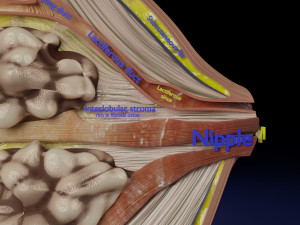

This is a 1:1 scaled model of right breast cut opened in sagittal plane to reveal its internal antomy and histology (schematic). The deeper parts and fascial layers are also depicted to give a very detailed approach to the model. The full layers starting from skin, nipple areola, till intercodtal muscles and ribs are also depicted.

breast mammary gland female chest wall anatomy human medical science reproductive genitalia muscle fascia milk nipple areola subcutaneous fatДо даного товару немає коментарів.